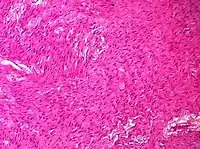

| Adult granulosa cell tumor | 1% | Almost 100% | Small, bland, cuboidal to polygonal cells in various patterns.[20] | ![]() | ||